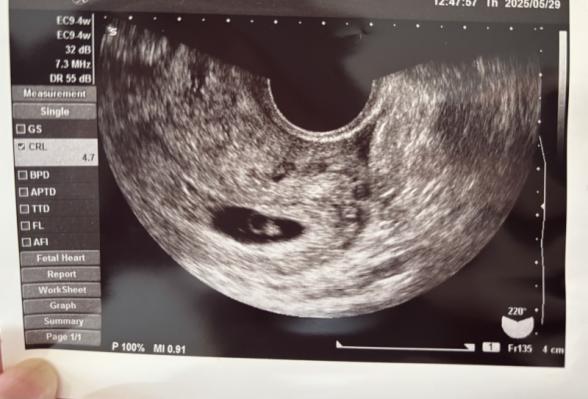

前回確認出来なかった胎芽を確認することができたのですが、4.7mmと週数的には小さいと言われました。

うっすらで私にはこれが胎芽?という感じです。

心拍も確認できず、流産の可能性が高いと言われました。